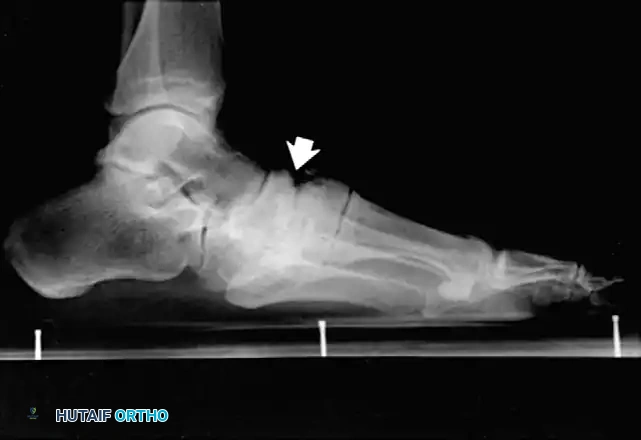

* Type 1 (Midfoot): Involves the tarsometatarsal (Lisfranc) and naviculocuneiform joints. This is the most common pattern, affecting approximately 60% of patients. It frequently results in a rocker-bottom deformity.

FIXED DEFORMITIES IN THE DIABETIC FOOT Surgical Diagram

If an ulcer is driven purely by a localized bony prominence in an otherwise stable foot (Eichenholz Stage III), a simple exostectomy may suffice. The most common site is the plantar-medial aspect of the midfoot (prominent medial cuneiform or base of the first metatarsal). Care must be taken to resect enough bone to relieve pressure without violating the remaining stabilizing ligaments, which could trigger a secondary collapse.

Lateral subluxation of the forefoot on the midfoot is the most common presentation of Type 1 Charcot. This produces an abducted forefoot, secondary hindfoot valgus, and a contracted Achilles tendon. Surgical correction involves a medial utility incision, resection of the destroyed TMT joints, realignment of the medial column, and rigid fixation using robust hardware (beaming screws, locking plates) or circular external fixation.

The Adducted Forefoot:

While less common, the adducted forefoot is notoriously difficult to treat. It is frequently precipitated by neuropathic fractures at the base of the fifth metatarsal. If the lateral column collapses and the forefoot adducts, massive pressure is transferred to the lateral border of the foot.

Surgical Warning: Simply excising the prominent fifth metatarsal base in an adducted Charcot foot is a critical error. It merely transfers the pressure apex proximally to the cuboid, leading to a new, more recalcitrant ulcer. Comprehensive realignment of the lateral column is required.